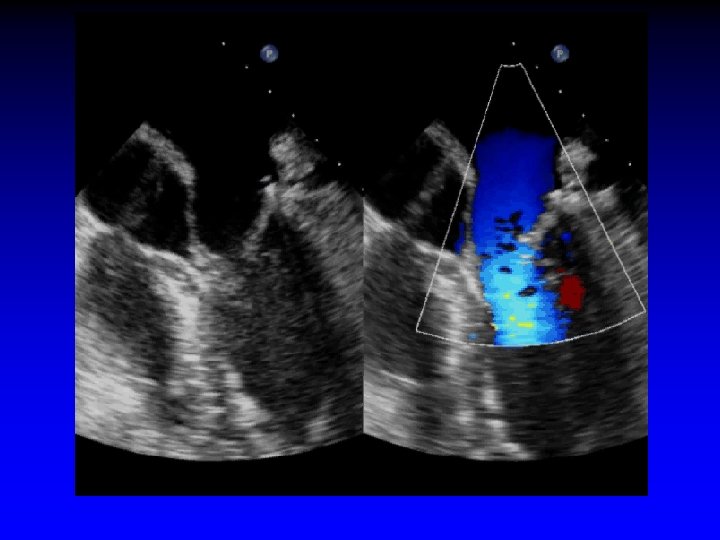

S/P repair